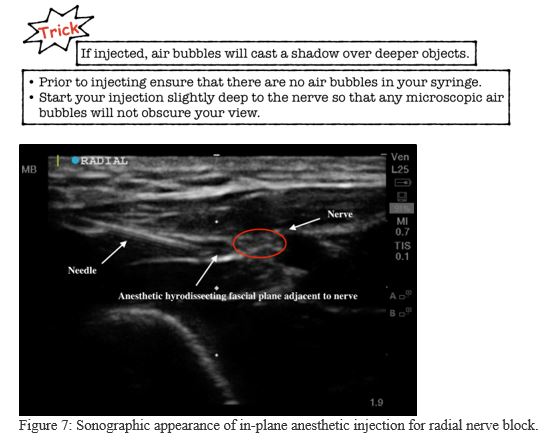

6. Inject the anesthetic (Figure 7)

Clean the injection site with chlorhexidine or alcohol and use an US probe cover to avoid any contamination of the injection site. This procedure should be done using a clean technique but does not require sterility. Hydro-dissect the fascial plane surrounding the nerve without penetrating the nerve bundle. The nerve bundle does not need to be completely surrounded by anesthetic. Anesthetic injected immediately adjacent to the nerve is usually sufficient.